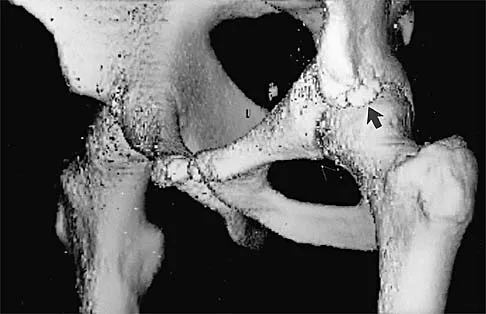

A 16-year-old high school football player sustains an injury to the left hip. The avulsed fragment identified by the arrow in Figure 34 represents the origin of which of the following structures?

Explanation